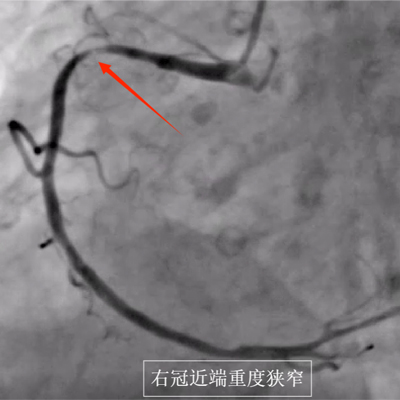

县人民医院为患者完善冠状动脉造影,提示前降支慢性闭塞,右冠极重度狭窄,相当于整个心脏供血均受影响,病情极其危险,随时可能再次出现生命危险 ,随后,心血管内科介入团队成功为其右冠快速并精准植入支架,解除患者右冠近端重度狭窄。手术后,患者的症状明显缓解,被安全送至心脏重症监护病房。